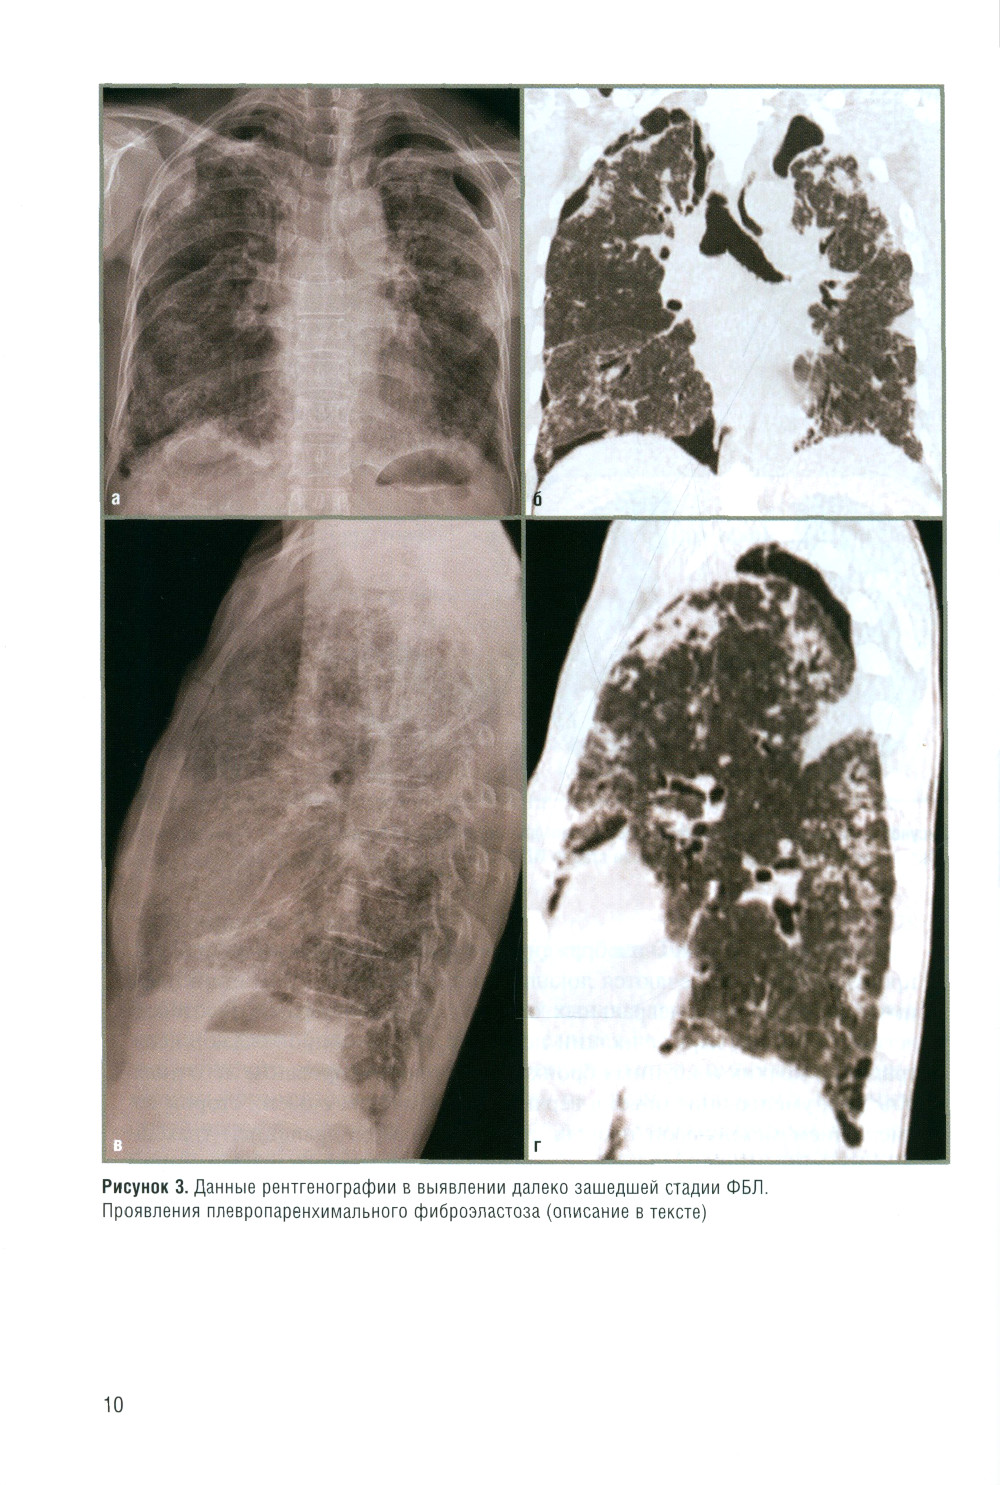

В книге рассматриваются лучевые проявления различных вариантов фиброзирующих болезней легких с позиции рентгенолога, принимающего участие в работе мультидисциплинарного консилиума. Автор выражает слова благодарности директору института НИИ интерстициальных и орфанных заболеваний легких д.м.н., профессору М.М. Ильковичу и его коллективу за возможность участвовать в этих разборах, где рентгенолог видит все сложности анализа клинических проявлений, лучевой и дифференциальной диагностики ФБЛ. В книге приведены примеры реальной работы рентгенолога (с некачественным лучевым архивом, сменой морфологических заключений, свидетельствующие о важности правильного лучевого алгоритма и методичности анализа лучевых исследований). Также приведены примеры нозологических заключений рентгенолога, без которых трактовка заболевания уходит в другую сторону и ухудшает его течение без своевременно начатого лечения.| Издательство | Элби |